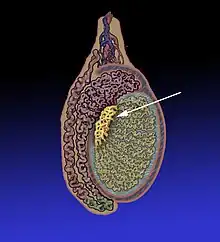

Position des canaux du rete testis dans un testicule humain adulte.

Le rete testis est un réseau de canaux des testicules issus des tubes séminifères droits dans le mediastinum testis.

Les canaux du rete testis s'écoulent dans les canaux efférents, qui passent dans la tête de l'épididyme. À ce niveau, le rete testis ne contient que des cellules de Sertoli, puisque tous les spermatozoïdes se trouvent dans la lumière des tubes séminifères.